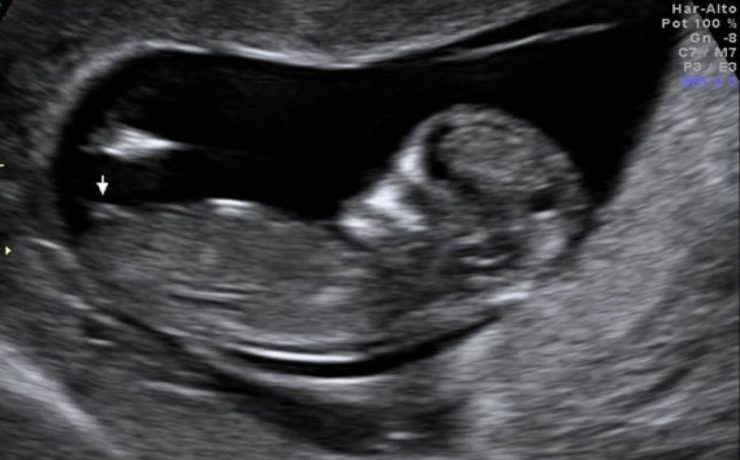

APENDICITIS DURANTE EL EMBARAZO

La apendicitis aguda durante el embarazo constituye la causa más frecuente de abdomen agudo quirúrgico no obstétrico, reportándose a nivel mundial una incidencia de 0.1 a 1.4 casos por cada 1,000 embarazadas. Algunos estudios en América Latina han reportado una incidencia aproximada de 1 por cada 1,200 embarazos. El diagnóstico